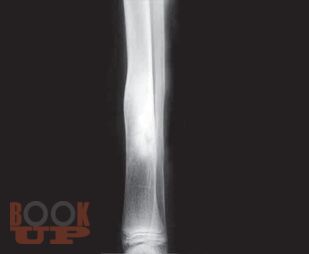

Thoroughly revised and updated with recent advances in the management of elective orthopedic conditions. Primer for orthopedic trauma has been included in annexures, enlisting commonly encountered fractures. Covers most of the questions asked in the postgraduate theoretical examinations. Difficult and advanced concepts are mentioned in points. Basic science in orthopedics has been discussed in detail. Sections are divided into body regions to establish correlation. New chapters added on Musculoskeletal Imaging, Preoperative Planning, Nanotechnology, Orthopedics in Digital Renaissance, Neglected Trauma to Bones and Joints (Annexure 4), expansion on Malunions, etc. Addition of lots of relevant figures and photographs along with tabulation. Various new diseases and techniques have been added. Enriched with more than 2200 relevant and beautiful illustrations.